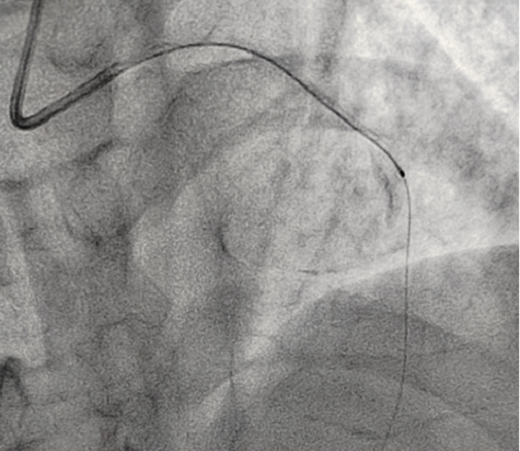

OCT檢測是將一條頭端帶光學透鏡的成像導管放在冠脈血管里,通過高速旋轉回撤,不到3秒鐘就可以幫我們診斷清楚血管里面的結構和斑塊性質,就像直接把眼睛放進血管里看一樣,整個診斷過程非常安全可靠。